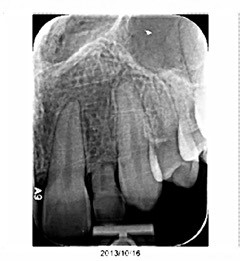

I’d like to introduce you to two patients in my practice. Caroline is a healthy, 23-year-old patient. She has a retained primary lateral incisor at tooth #10 that is decalcified and unesthetic. The tooth has undergone bone replacement and root resorption. As a result, it’s ankylosed but has acceptable bone and adequate facial prominence. An immediate implant and immediate provisional are considered the ideal treatment for replacement.

This intimacy is referred to as the bone-to-implant contact. It is a function of both the implant length and diameter (BIC). This intimate contact provides the primary stability of the implant. Acceptable stability is verified through the torque testing at the time of placement. 50 Ncm or greater torque is considered acceptable for immediate implant loading.

Regardless of the BIC, micro and mini “gaps” exist at the bone/implant interface. These “gaps” fill with blood and ultimately form clots. Ideally, bone will replace these clots through resorption/replacement. The oxidized layer of the titanium implant creates a cellular response that promotes adhesion and cellular proliferation. This is the “structural” component of healing implants. The “static” aspect of primary stability is essential to allow adequate healing to occur before “loading” of the implant.